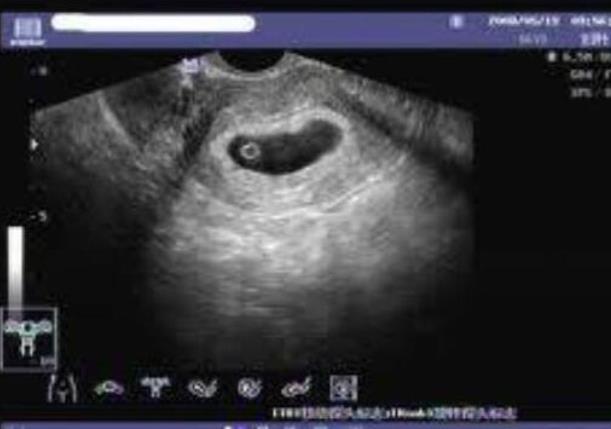

子宫内膜

我们要知道的就是,大连生殖中心试管婴儿之所以能够有着较高成功率,就是因为他们在各个方面都善于把控子宫里面,其实对于试管婴儿成功率来说也是有很大的影响,子宫里面会成为影响妊娠率的重要条件,好的子宫内膜在胚胎植入之前能够提供良好的条件,不好的子宫内膜同样就像是一个贫瘠的土壤一样,所以说优良的种子也很难在这其中进行生长,那么子宫内膜的机械损伤以及子宫肌瘤,还有子宫腺肌症,可以不同程度地影响我们吸烟或者是体重指数过高,精神因素也会影响成功率。